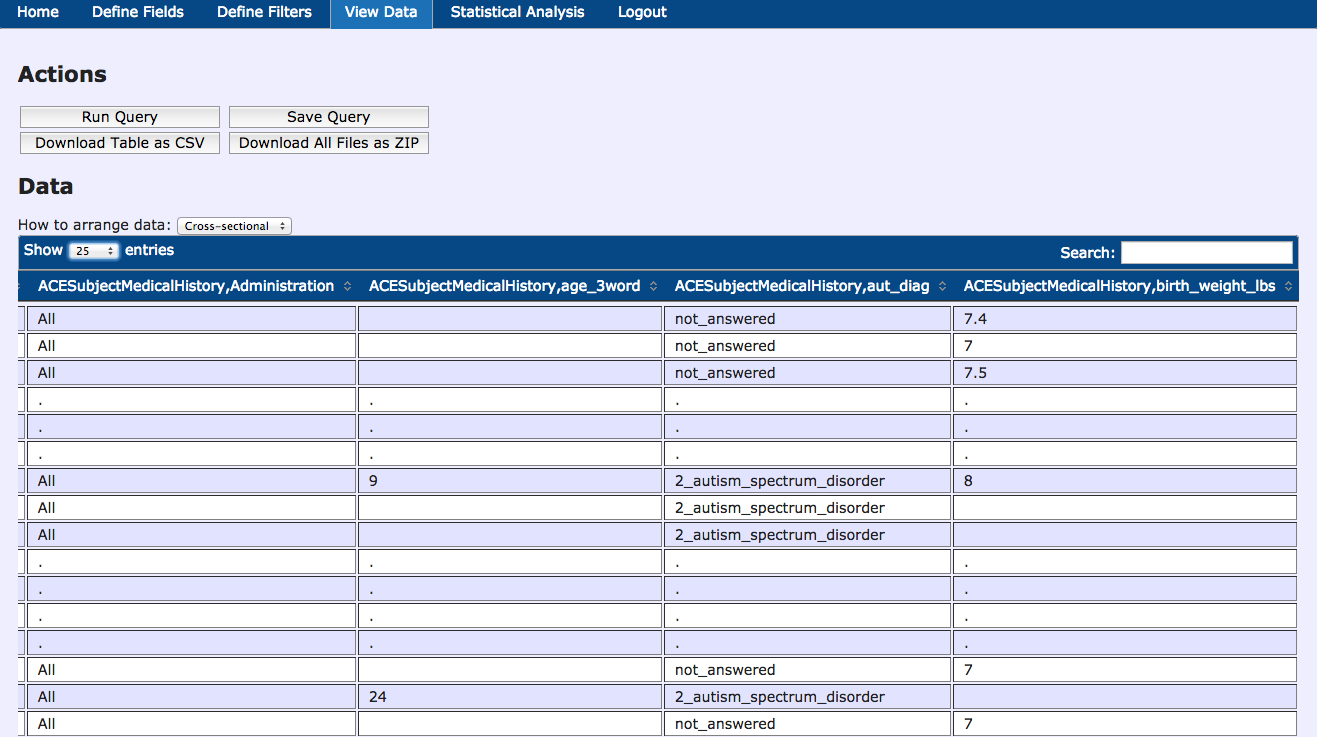

Data Querying Tool - Results

Data Querying Tool - Statistics

- Multimodal Data Querying - Easy querying of data, without requiring a programmer